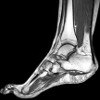

MRI of the foot.

Магнитно-резонансная томография стопы. Методика диагностики визуализации слоя за слоем тканей с использованием определенных свойств ядер атомов водорода при их возбуждении радиоволнами в мощном магнитном поле. Обычно проводится для уточнения диагноза после рентгенографии стопы. Позволяет оценить состояние костей, мелких суставов (межфаланговых, плюсневых, метатарзальных), мышц, сухожилий, связок и сосудов стопы. Он используется для выявления воспалительных процессов, травматических повреждений, опухолей, нарушений развития и нарушений кровообращения. Он проводится при артрите, артрите, переломах, переломах связок и мышц, остеомиелите, глубоком абсцессе стопы, новообразованиях, анкилозе, контрактурах, нарушениях кровообращения и глубоких неметаллических инородных телах стопы.